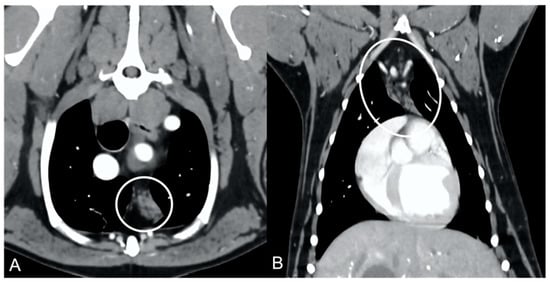

In both groups, most of the dogs presented with a triangular thymus (Figure 1); in the adult group, some dogs had an elongated thymus, and in the juvenile group, some dogs had a flattened thymus (Figure 2).

The overall appearance was lobulated in all of the adult dogs and homogeneous in all of the juvenile dogs (Figure 1 and Figure 3). The thymus was left-sided in all of the adult dogs, while it was located in the midline in a few juvenile dogs; one presented a thymus on the right side due to situs inversus (Figure 4). The maximum dimension of the thymus in the adult dogs group was always the length, while in some juvenile dogs, the maximum diameter was the width (Figure 2). The dimensions of the thymus were variable between different patients, with several breeds included and large differences in body weight between the dogs. For this reason, a ratio between the maximum diameter of the thymus (measured in cm) and the body weight (measured in kg) was calculated for each dog. The median ratio in the adult dogs group was 0.2 (minimum: 0.06; maximum: 0.4), while in juvenile dogs, it was 0.4 (minimum: 0.1; maximum: 1.4). The dogs with the higher ratio (>1) were in the juvenile group and they presented with spinal a cyst and enteritis and were 6 and 7 months old, respectively. The dogs with the lower ratio (<0.1) were in the adult group and they presented with muscular hemangiosarcoma (one dog) and synovial cell sarcoma (two dogs) and were 2, 6, and 8 years old, respectively.

Figure 2. Example of a flattened thymus (circled) in a young dog. Post-contrast dorsal CT reconstruction (A) and transverse image (B) of the same patient. Note the flattened appearance of the thymus, enlarged in the laterolateral direction (width) and smaller in the dorsoventral direction (thickness).